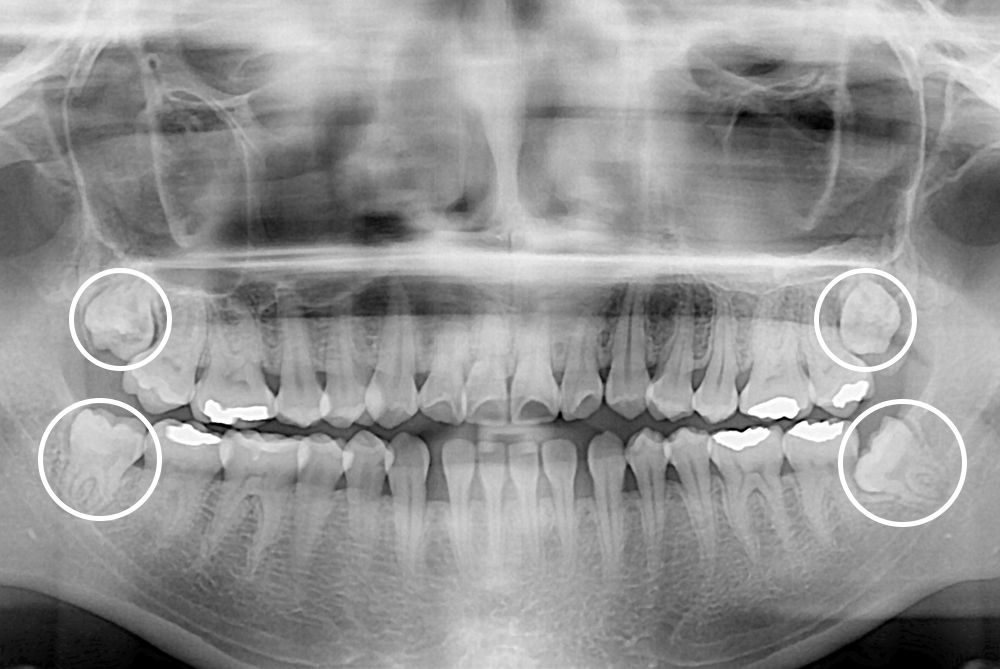

[사랑니] 매복 사랑니 발치

치료전 : 2019-06-04

세종치과는 구강악안면외과학 박사이신 원장님이 발치하는 치과입니다.